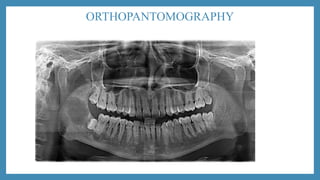

• Orthopantomography

ORTHOPANTOMOGRAPHY